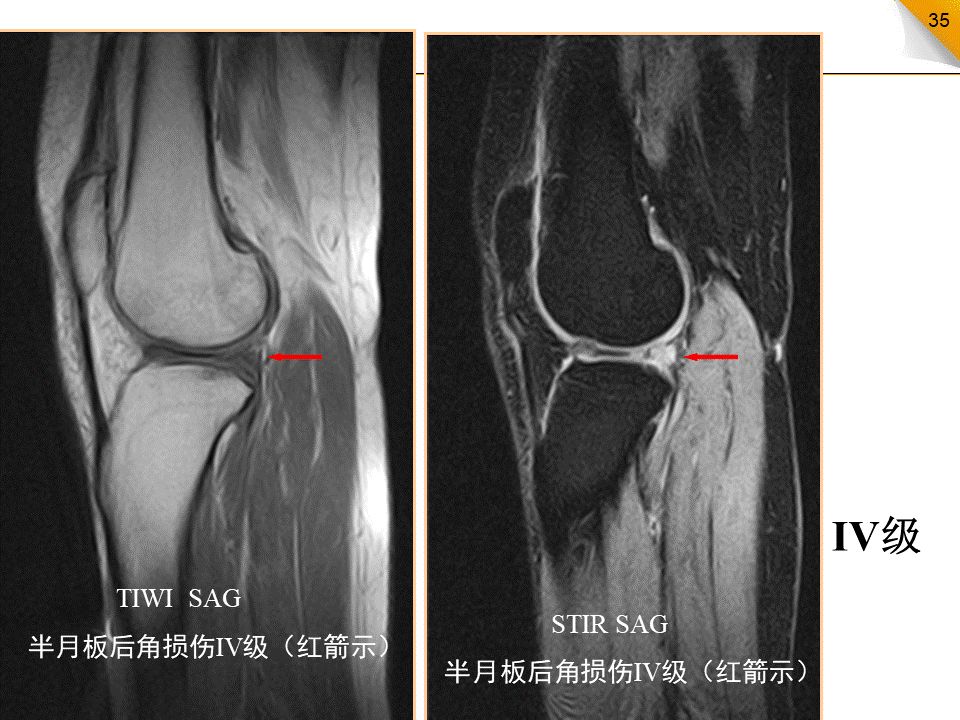

半月板损伤的MR分级

0级:正常半月板,均匀的低信号,形态规则I级:不与半月板关节面相接触的灶性信号增高影II级:半月板内线性信号增高,可延伸至半月板的关节囊缘,但未达到半月板的关节面缘,是I级信号改变的继续,范围更广III级:半月板内的高信号达到半月板的关节面,代表半月板的撕裂IV级:半月板破碎成多块并向关节腔内移位